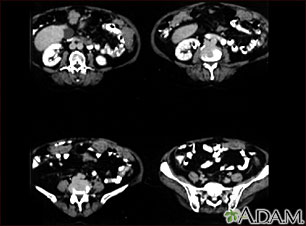

A CT scan series of the lower abdomen showing ovarian cancer that has metastasized (spread) to the peritoneum.